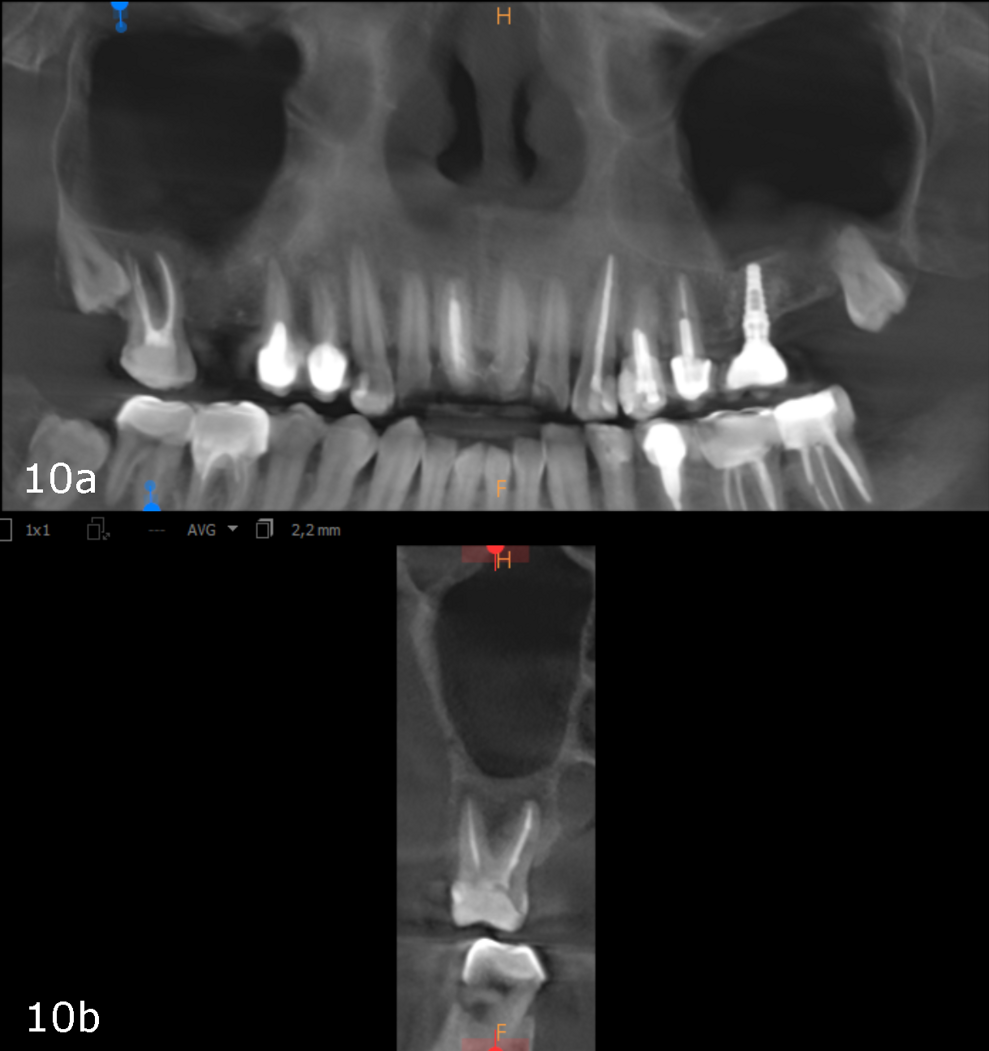

Figs. 10a & b: CBCT scan taken 12 weeks later showing complete healing, panoramic view (a) and cross-section of tooth #17 (b).

The bottom line is that it is really essential to locate the origin of our patients’ problem and evaluate its consequences to give proper treatment that facilitates complete regeneration of not only the periapical area but also the entire area of the paranasal sinuses (Figs. 10a & b). This can help the body and the immune system to achieve miraculous healing with a non-invasive treatment protocol.